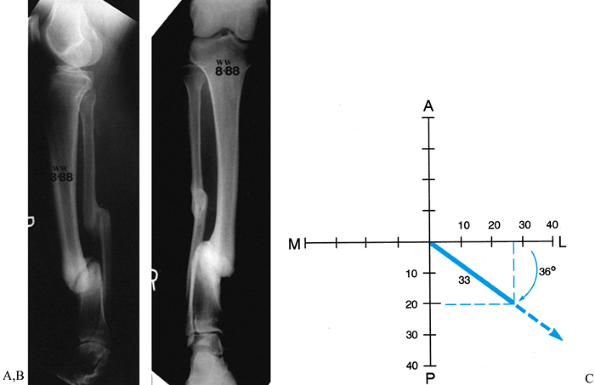

Preoperative determination of tibial deformity with a normal femur is

![]() |

Figure 32.18. A:

The apparatus for correction of this angular deformity is preconstructed with two levels of fixation on either side of the hinge. The hinge level, plane, magnitude, and direction are built into the apparatus. Tibial diaphyseal deformity with a normal femur. Step 0: Draw the mechanical axis line to demonstrate the degree of mechanical axis deviation created by the obvious tibial diaphyseal deformity. The malalignment test was performed to confirm that the orientation of the distal femur is normal. Step 1: Since the femur is normal, draw the line from the center of the hip through the center of the knee and extend it distally. This is the mechanical axis of the proximal tibia. Step 2A: Draw a line from the center of the plafond extending proximally in line with the anatomic axis of the tibia. This is the mechanical axis of the distal tibia. The center of rotation of angulation is at the intersection of the two mechanical axis lines. The angular deformity measures 26°. Step 2B: The alternative method is to draw a line down the convex cortices of the deformity. These lines intersect at the same level and also demonstrate a 26° deformity. Step 3A: The deformity correction is performed on paper at the level of the apex of the deformity for a total of 26°. This realigns and overlaps the mechanical axis lines to reestablish the colinearity of the hip-knee-ankle axis. Step 3B: After opening wedge correction. This osteotomy also realigns the diaphyseal line of the convex cortex so that it is colinear. B: Tibial frame applied to correct deformity illustrated in A. |